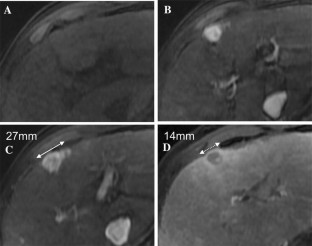

The Liver Imaging Reporting and Data System (LI-RADS) was designed to standardize the interpretation and reporting of observations seen on studies performed in patients at risk for development of hepatocellular carcinoma (HCC). The LI-RADS algorithm guides radiologists through the process of categorizing observations on a spectrum from definitely benign to definitely HCC. Major features are the imaging features used to categorize observations as LI-RADS 3 (intermediate probability of malignancy), LIRADS 4 (probably HCC), and LI-RADS 5 (definite HCC). Major features include arterial phase hyperenhancement, washout appearance, enhancing capsule appearance, size, and threshold growth. Observations that have few major criteria are assigned lower categories than those that have several, with the goal of preserving high specificity for the LR-5 category of Definite HCC. The goal of this paper is to discuss LI-RADS major features, including definitions, rationale for selection as major features, and imaging examples.

Fig. 1